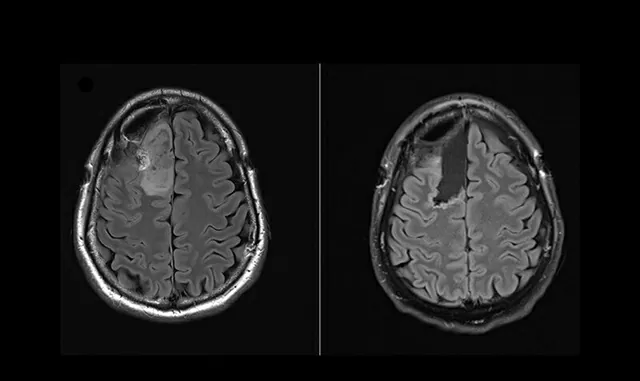

Thông qua quan sát mẫu khối u trước và sau khi dùng thuốc, nhóm nghiên cứu từ Bệnh viện Hoàng gia Melbourne (RMH) và Trung tâm Ung thư Peter MacCallum trực tiếp chứng kiến sự thay đổi tích cực trên tế bào ung thư.

Trong khi đó, bác sĩ Jim Whittle làm việc tại Trung tâm Ung thư Peter MacCallum - trưởng nhóm nghiên cứu trên - cho biết, các thử nghiệm kiểu lấy mẫu sinh thiết trước và sau điều trị để đo lường tác động vốn phổ biến ở nhiều loại ung thư khác, nhưng vì sự phức tạp của phẫu thuật thần kinh nên chưa từng áp dụng cho u não.

Nghiên cứu chứng minh rằng, BrainPOP là nền tảng an toàn, hiệu quả, bộc lộ tác động chi tiết của thuốc trong não, qua đó tạo điều kiện để gia đình bệnh nhân đưa ra quyết định điều trị cá nhân hóa.